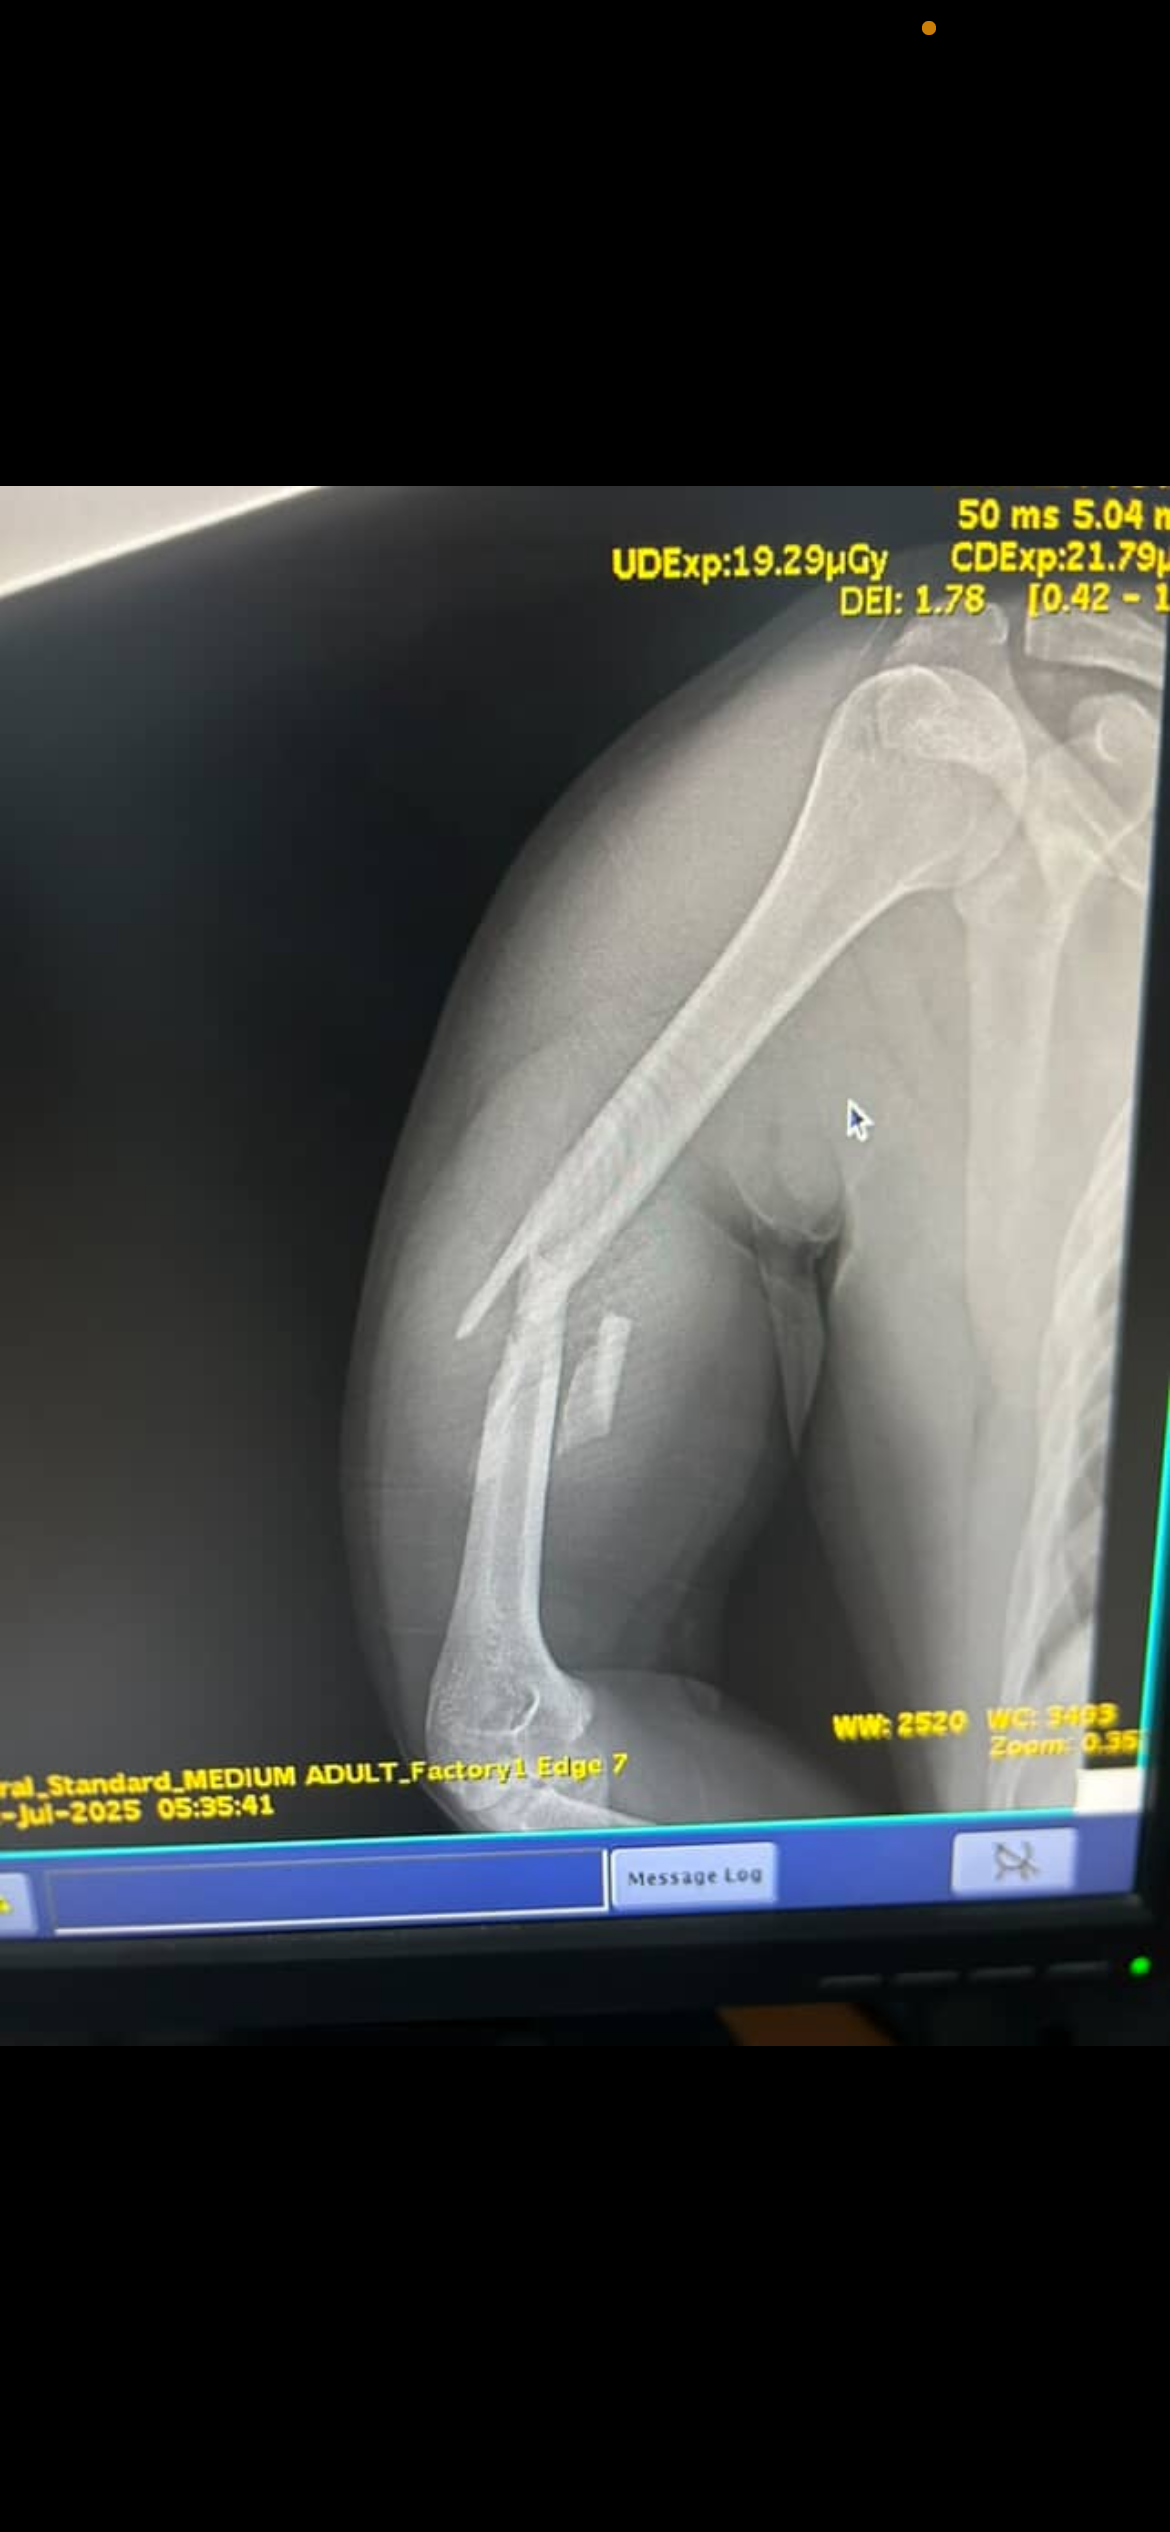

He is currently heavily sedated, with multiple broken bones, including life-threatening internal injuries.